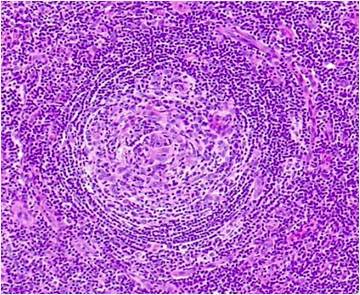

En febrero de 2019 decidió continuar el seguimiento médico de su enfermedad en nuestra institución. En dicho momento se encontraba asintomático, sin parámetros de actividad de la enfermedad y con carga viral de VHH8 no detectable. En diciembre de 2020 presentó recaída de la enfermedad con síntomas B, citopenias y valores de ferritina elevados. Se realizó una nueva biopsia escisional, en la cual se confirmó el diagnóstico mediante morfología e IHQ, evidenciando alteraciones en el tejido y células LANA-1 positivas en la zona del manto (Figuras 1 y 2). Adicionalmente, se realizaron estudios complementarios y de laboratorio para la evaluación del estado de la enfermedad. En estudios por imágenes se observaron ganglios linfáticos aumentados en zona infra y supra diafragmática, hepato-esplénicos y mediastinales. Recibió tratamiento con rituximab y doxorrubicina liposomal, logrando una segunda remisión completa.

Figura 1

Biopsia de ganglio axilar derecho. Corte histológico teñido con hematoxilina eosina (40x). Se observa un folículo linfoide con centro germinal atrófico e hiperplasia de la zona del manto con linfocitos dispuestos en capas concéntricas. |